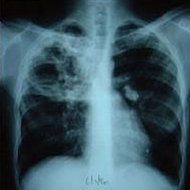

„Obiceiul de a fuma predispune nu numai la bronsita cronica si emfizem, dar si la cancer pulmonar. Iar pentru bolile de inima este unul dintre cei cinci factori majori de risc- fumatul. In concluzie, daca amandoua coexista, obezitatea si fumatul, riscurile nu numai ca se aduna, dar se amplifica”, a afirmat prof. dr. Mihai Voiculescu, Seful Centrului de Medicina Interna de la Institutul Fundeni.